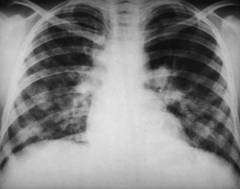

Рентгенография грудной клетки Рентгенография грудной клетки помогает выявить метастазы опухоли в легкие, внутригрудные лимфатические узлы. Рентгеновские снимки грудной клетки делают в прямой (анфас) и боковой (профиль) проекции.